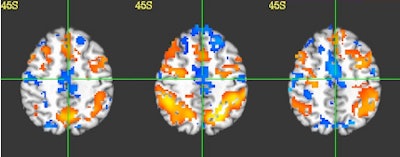

![]() |

| Functional MRI images of a high school football player with no other impairments or concussions show consistent fMRI activity from preseason (left) to in-season (middle) and postseason (right) images. Orange region denotes greater activity for the two-back test compared to the one-back, compared to the blue region, which shows less activity. All images courtesy of Purdue Acute Neural Injury Consortium. |

Specifically, the most consistent impairments in changes in the fMRI activation were a decrease in activity in the posterior temporal lobe, which resulted in the athletes having impaired language and memory. Among the four control subjects, the analysis found no consistent changes in their fMRI brain activation.